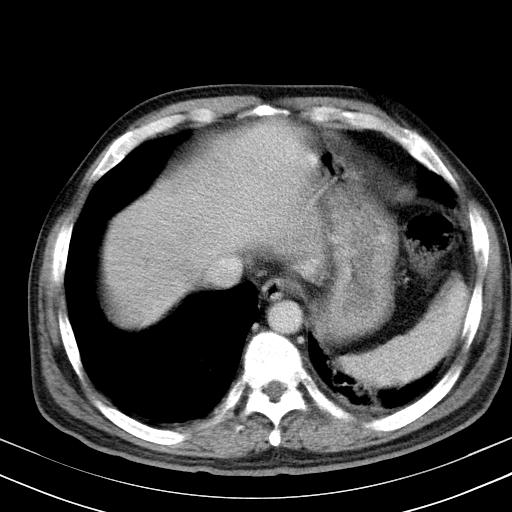

标题: 肝脏

大家看看肝脏右叶片状低密度影是什么改变啊?

淋巴瘤?肝脏请增强后说啊

多发肿大淋巴结影,肝内改变需结合强化观察

多发肿大淋巴结影,肝内改变需结合强化观察。